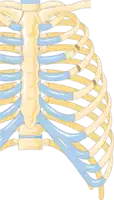

Illustration showing rib fracture at 3rd, 4th and 5th rib.